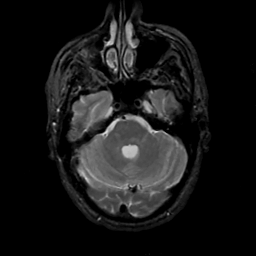

MR Study #12, May 12, 1991 -- Slice #13

[Home][Help][Clinical][Tour 1][Tour 2] Slice 13